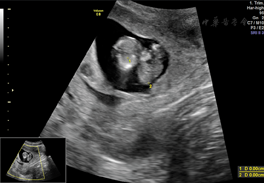

孕妇26岁,孕1产0,孕12+5周,以外院诊断腹部囊实性包块来我院进一步检查。患者及其配偶体健,无其他病史及不良习惯,家族中无类似患者,患者否认直系三代有遗传病史及遗传倾向疾病。二维超声检查:胎儿颅骨光环完整,双侧脉络丛发育正常;胸腔内未见明显异常,心脏可测得四腔心、左右室流出道;胎儿腹部可测及大小约2.28 cm×1.9 cm的囊实性包块,向外突出,其内可见胃泡,另见一囊性无回声,大小约2.0 cm×1.8 cm,两侧可见脐动脉;胎儿下腹部囊性包块左侧测及两条平行骨性回声,可见一侧脚板;双上肢可见;胎儿肾及肾动脉显示不清;胎儿脊柱腰段弯曲,骶尾部测及一囊性无回声区,直径约0.36 cm(图1,图2,图3)。超声提示:胎儿先天性多发复杂畸形;胎儿人鱼序列综合征;胎儿腹部囊实性包块(腹裂不能除外);胎儿巨膀胱;胎儿脊柱裂伴侧弯。引产标本:胎儿头面部未见明显异常,双上肢可见,胸腔正常,腹腔内器官外翻、巨大膀胱,胎儿双下肢融合,可及双侧骨性结构,双足可见。与超声检查结果相符,遂行胎儿染色体检查,核型正常。